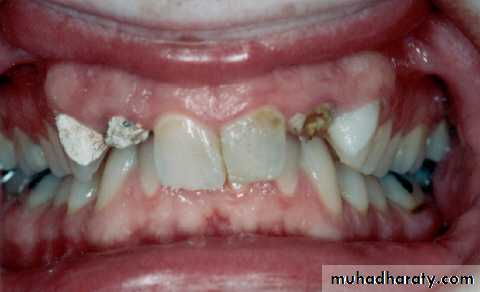

a. Clinical examination

8